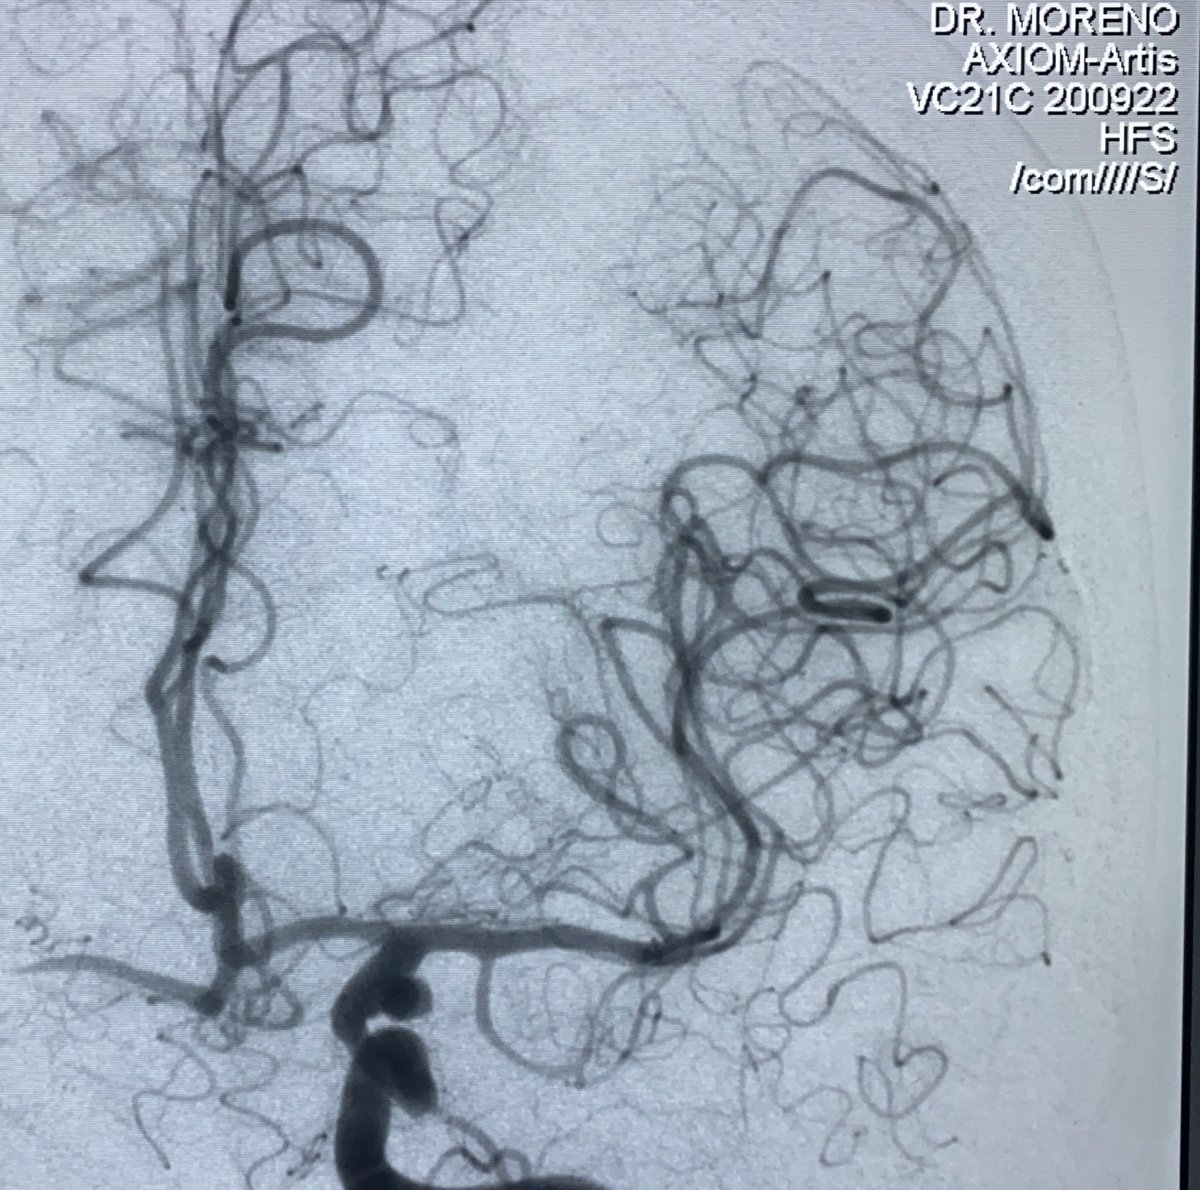

Ceki Sagiz, especialista de producto de BALT, nos explica las posibles soluciones endovasculares a un aneurisma de bifurcación de arteria cerebral media derecha. #tratamientoendovascular #middlecerebralartery #aneurysm m.youtube.com/watch?time_con…